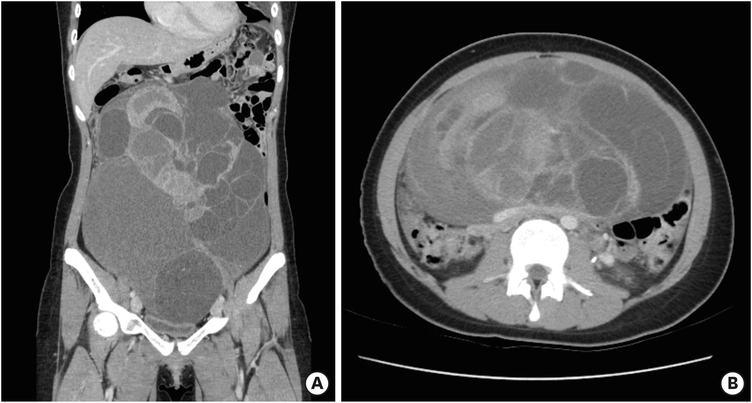

The patient #5 is demonstrated as a representative case. A previously healthy 17-year-old female patient suffered from abdominal distension. She was diagnosed with left ovarian epithelial cancer. According to the CT image, 21 cm sized huge cystic mass with septation and solid portion inside was observed (Fig. 2A). Also, left paraaortic and left renal-hilum lymph node enlargement were identified (Fig. 2B). She underwent LSO, PLND, and PALND. The pathology of left ovary was mucinous cystadenocarcinoma. In microscopic view, multilocular cystic spaces lined by intestinal type mucinous epithelium with occasional papillary projection. Some foci of destructive stromal invasion are occasionally seen, so the pathologic diagnosis is mucinous cystadenocarcinoma (Fig. 3).

Fig. 2

Computed tomography of patient #5. (A) Coronal image, 21 cm-sized huge cystic mass with septation and solid portion, (B) axial image, left paraaortic and left renal-hilum lymph node enlargement.